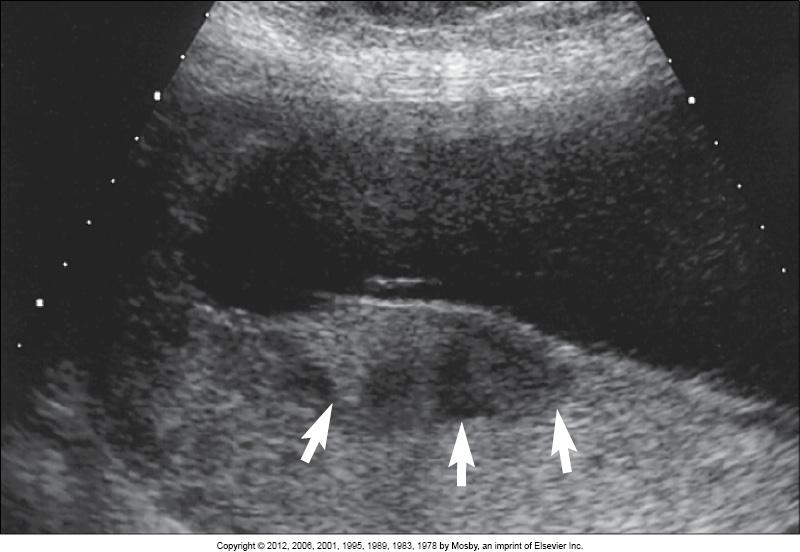

What are the arrows pointing to?

circumvallate/circummarginate placenta